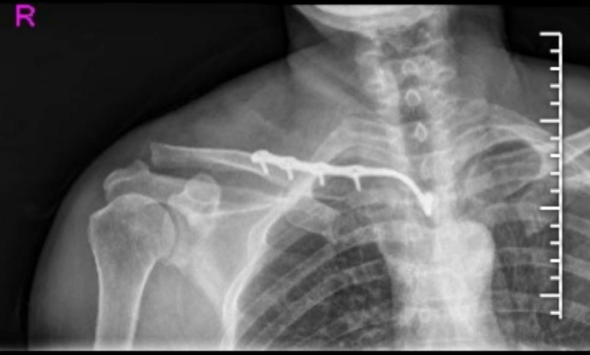

Plain Radiographs (DR): Standard anteroposterior (AP) and 45-degree cephalic tilt (serendipity) views are essential for initial assessment. These help evaluate fracture displacement, comminution, and SC joint alignment. However, complex anatomy and overlapping structures often limit their diagnostic utility for the medial clavicle.

Figure: Pre-operative DR demonstrating a right proximal clavicle fracture. -